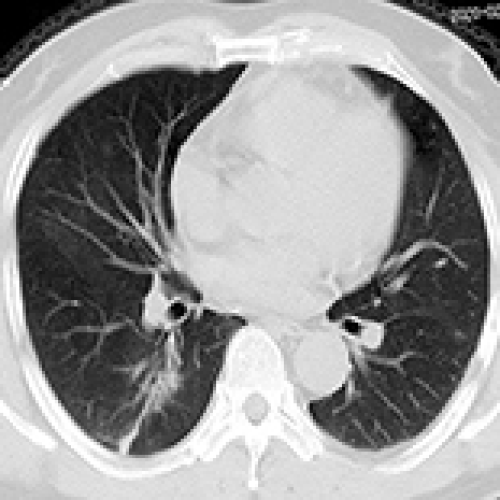

14 Nov 2021 : Clinical Research

Clinical Features and Temporal Lung Radiographic Changes in 25 Patients Recovering from COVID-19 Pneumonia: A Retrospective Case-Control Study

Chao Hu, Jian Ping Zeng, Ke Peng, Hong Xia, Huan Ming Zhang, Zhi Zhong, Ming Yan Jiang

3,640 973 0